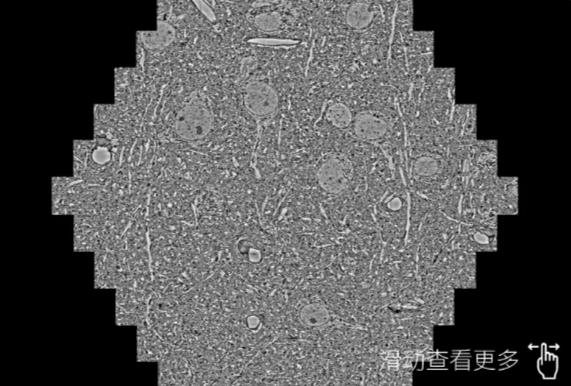

鼠脑切片。左图使用临汾蔡司临汾扫描电镜MultiSEM706对165μmx143pm面积区域成像,耗时仅需1.5秒。右图为鼠脑切片中30μm区域放大效果。样品由芝加哥大学B.Kasthuri提供。

使用蔡司高速临汾扫描电镜MultiSEM对1mm²人脑皮层组织进行高分辨成像,并对其中的各种细胞结构进行三维重构分析。左图展示了2x3mm²组织平面中锥体神经元的三维重构效果。右图显示了局部体积神经元三维重构。图像由哈佛大学chtman实验室提供,渲染图由D. Berger 制作。